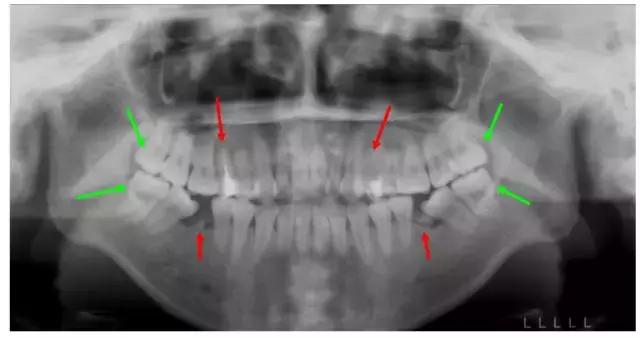

普瑞美口腔——欧阳莉医生案例:

这个妹子正畸前,前牙不能咬合,牙凸又嘴凸而且还有残余的牙根,牙列开始倾斜。综合考虑后,医生拔除了箭头所示8颗牙,没有采取常规拔牙,因为需要尽量拔除不能保留的病牙。

矫正结束后,姑娘收获了整齐的牙齿和完美的微笑~